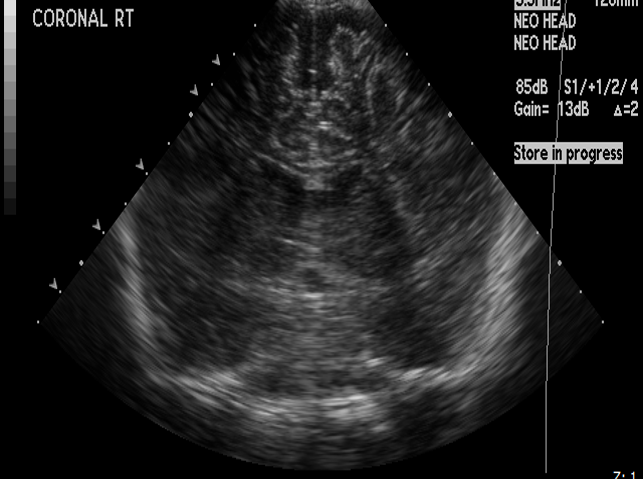

Info Images Findings Impression Reco/Acuity Case Images View Images / Launch Visage Case Notes History Full term infant. We are asked to evaluate posterior fossa cyst. Exam Gray scale and Doppler Ultrasonographic examination of the head. Prior Study N/A Dicom View Reference Material

Section 1 Submit Findings Case149 Findings Brain The brain is immature. Yes No There is under-sulcation and open sylvian fissures. Yes No There is/are multiple hypoechoic areas in the periventricular white matter. Yes No There is/are multiple hyperechoic areas in the periventricular white matter. Yes No There is diffuse cerebral edema with diffusely increased echogenicity of the brain parenchyma and loss of grey white matter differentiation. Yes No The thalami/basal ganglia are hypoechoic. Yes No There is periventricular calcification. Yes No There is intra-parenchymal calcification. Yes No CSF spaces/ventricular system There is a prominence of the extra axial fluid spaces. Yes No There are debris/septations in the extra axial fluid spaces. Yes No There are debris/septations in the ventricles. Yes No There is a subdural collection on the right/left side. Yes No There is prominence of the ventricular system. Yes No There is an asymmetry of the ventricular system. Yes No There is a cavum septum pellucidum. Yes No There is a midline shift towards right/left. Yes No The choroid plexus is bulky/lobulated. Yes No There is a choroid plexus cyst measuring… Yes No There are debris/clots in the occipital horn. Yes No There is a posterior fossa cyst measuring… Yes No The tentorium is elevated/depressed. Yes No The lateral ventricle/s are dilated. Yes No The third ventricle is dilated. Yes No The 4th ventricle is dilated. Yes No There are pseudo cysts. Yes No Germinal matrix hemorrhage (Only in the premature infants): Please do not answer if the patient is a full term. There is a germinal matrix hemorrhage, consistent with a grade I hemorrhage. Yes No There is an intraventricular extension consistent with a grade II hemorrhage. Yes No There is an intraventricular extension with the dilatation of ventricles, consistent with a grade III hemorrhage. Yes No There is an intra-parenchymal extension, consistent with grade IV hemorrhage. Yes No On color Doppler examination, the Resistive index in the anterior cerebral artery is… There is a loss of the diastolic flow on the Doppler exam. Yes No There is altered vascularity on Doppler imaging. Yes No There is an AVM in the region of… Yes No